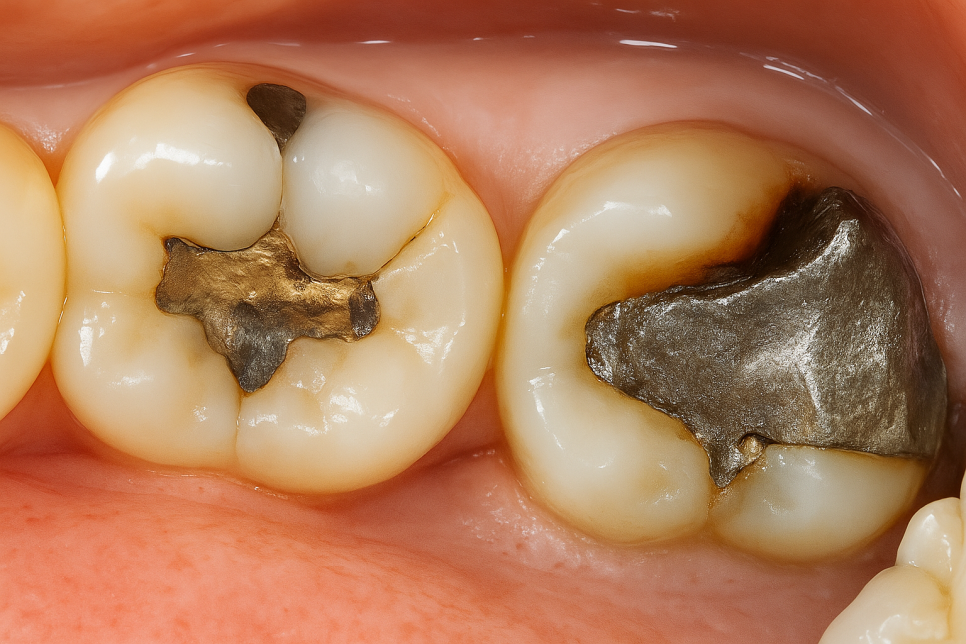

보철 하방 이차우식

사진을 보시면 기존에 수복한 인레이 주변으로

검게 충치를 확인해 볼 수 있습니다.

오랜 기간 보철을 사용하면서 접착제가 마모되어

변연이 누출되면서 사진처럼 이차 우식이

진행될 수 있습니다.

충치로 인하여 치질이 점차 약해지면서

약한 충격에도 파절될 수 있으며,

기존 보철이 쐐기 작용을 하면서

파절 라인이 점차 깊어지고 범위가 넓어집니다.

또한 일전에 치아를 어느 정도 다듬었기 때문에

보철 사이 틈으로 세균이 들어가 이가 썩으면,

겉질이 아니라 속질까지 손상됩니다.

단단한 겉질과 반면 속질은 무르기 때문에

진행속도가 훨씬 빠르죠.

그렇기에 이런 경우, 빠르게 발견해서

조치를 취하는 것이 중요합니다.